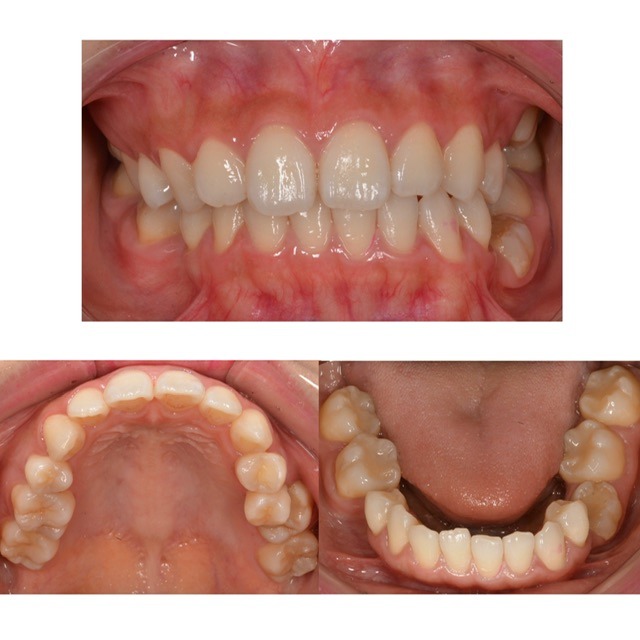

歯並びを綺麗にしたい 30代男性 2026.2.18

主訴・術前 歯並びを治したい 術後の患者様の感想 長年、歯並びにコンプレックスがあり笑うのに抵抗がありました。 矯正治療は諦めていましたが、こちらでは歯を抜かずに3年という早さでここまで綺麗に治療していただけて本当に感謝…